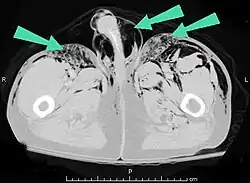

| An abdominal CT scan of a patient with subcutaneous emphysema (arrows) | |

Significant cases of subcutaneous emphysema are easy to diagnose because of the characteristic signs of the condition.[1] In some cases, the signs are subtle, making diagnosis more difficult.[13] Medical imaging is used to diagnose the condition or confirm a diagnosis made using clinical signs. On a chest radiograph, subcutaneous emphysema may be seen as radiolucent striations in the pattern expected from the pectoralis major muscle group. Air in the subcutaneous tissues may interfere with radiography of the chest, potentially obscuring serious conditions such as pneumothorax.[18] It can also reduce the effectiveness of chest ultrasound.[28] On the other hand, since subcutaneous emphysema may become apparent in chest X-rays before a pneumothorax does, its presence may be used to infer that of the latter injury.[13] Subcutaneous emphysema can also be seen in CT scans, with the air pockets appearing as dark areas. CT scanning is so sensitive that it commonly makes it possible to find the exact spot from which air is entering the soft tissues.[13] In 1944, M.T. Macklin and C.C. Macklin published further insights into the pathophysiology of spontaneous Macklin's Syndrome occurring as a result of a severe asthmatic attack.